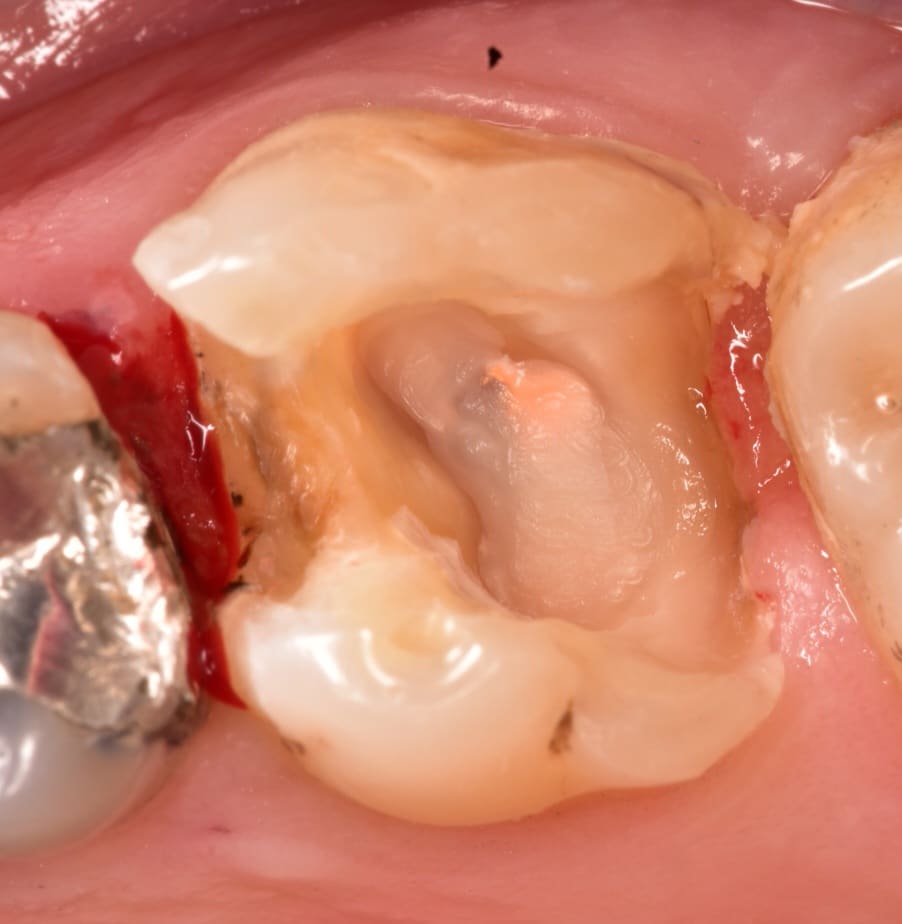

Old TF and amalgam removed, all caries removed

Isolation, after endo_treatment the minimum thickness needed to the wall is 3 mm if it's less than 3 mm the walls must be reduced